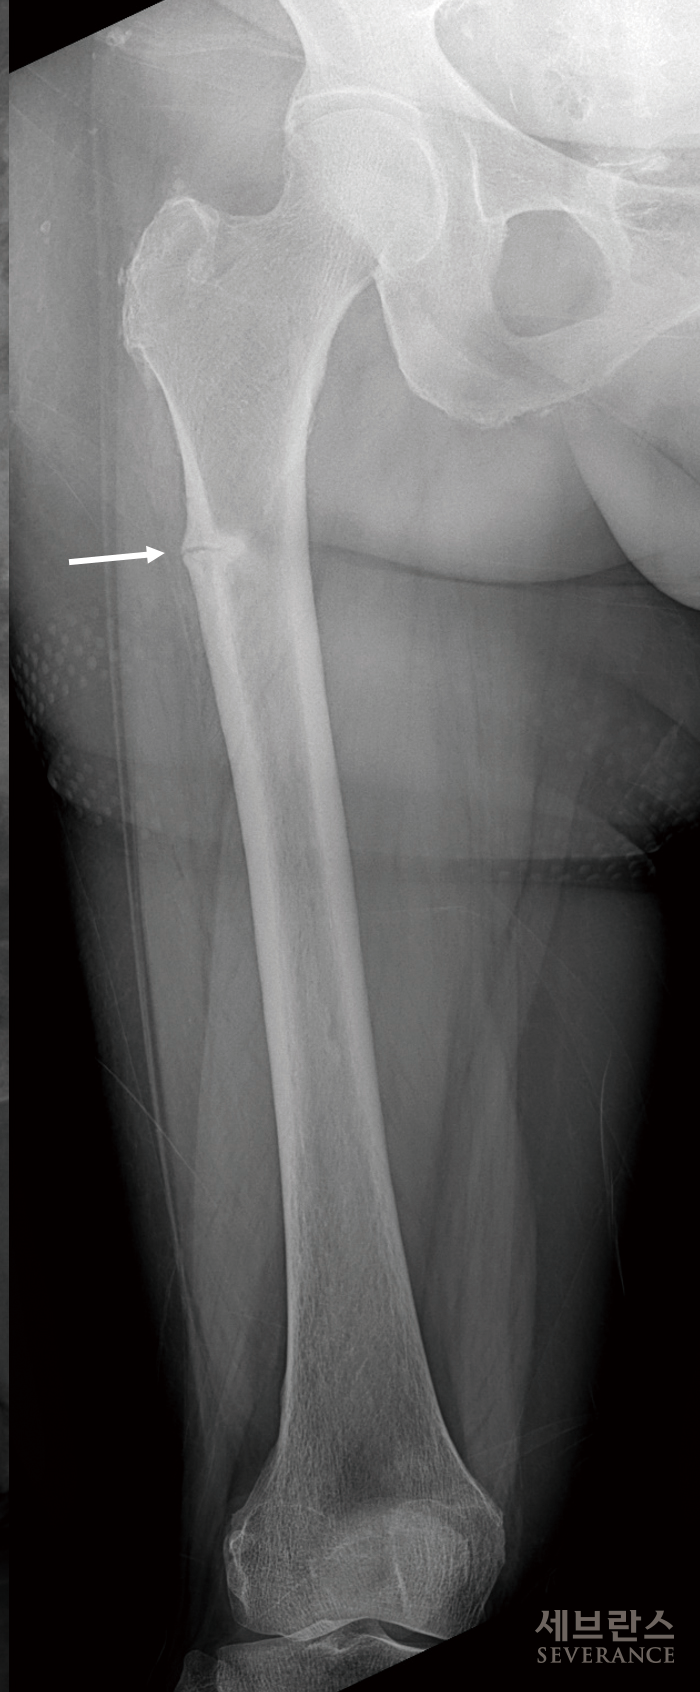

비정형 대퇴골 골절

*비정형 대퇴골 골절이란? 발생 원인은 명확하지 않으나 주로 골다공증 치료를 오래 지속한 환자에서 대퇴골 전자 하부 또는 몸통부의 바깥쪽에 금이 가다가 골절되는 것으로, 일반적인 대퇴골 골절과 달리 질환의 일종입니다. 뚜렷한 외상이 없거나 가벼운 외상으로도 골절이 일어나고, 특이한 골절 형태를 보입니다. |